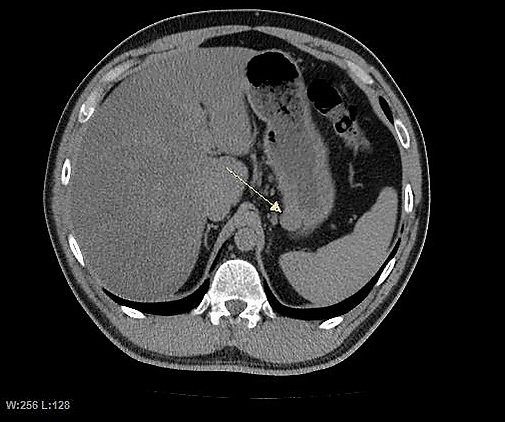

Крупные ГИСО

По мере роста опухоли, она может проецироваться снаружи от органа (экзофитный рост) и/или в просвете органа (интралюминальный рост); чаще всего ГИСО растут экзофитно, таким образом большая часть опухоли располагается в проекции брюшной полости. Если увеличение объёма опухоли опережает рост её кровоснабжения, опухоль может некротизироваться в толще, с формированием центральной зоны жидкостной плотности и кавитацией, что может приводить к изъязвлению и формированию соустья с полостью органа. В этом случае исследование с бариевой взвесью может демонстрировать газ, уровни газ/жидкость или депонирование контрастного препарата в этих областях.[17][18] При КТ с контрастным усилением крупные ГИСО выглядят негомогенно, в связи с неоднородностью структуры опухоли, обусловленной участками некроза, кровоизлияниями и полостями, что радиологически проявляется контрастированием опухоли преимущественно по периферии.[16]

Злокачественность может проявляться локальной инвазией и метастазами, обычно в печень, сальник и брюшину. Однако встречаются случаи метастазирования в кости, плевру, лёгкие и забрюшинное пространство. По сравнению с аденокарциномой желудка или лимфомой желудка/тонкой кишки, злокачественная лимфаденопатия при ГИСО не типична (<10 %).[16] При отсутствии метастазов радиологическими признаками злокачественности являются большие размеры опухоли (>5 cm), гетерогенное контрастирование после введения контрастного препарата и наличие изъязвлений.[3][16][22] Также явно злокачественное поведение (без учёта опухолей со злокачественным потенциалом) реже наблюдается при ГИСО желудка, с отношением доброкачественных опухолей к явно злокачественным 3-5:1.[3] Даже в случае наличия радиологических признаков злокачественности, следует учитывать, что они могут быть обусловлены другой опухолью; окончательный диагноз должен быть установлен иммуногистохимическим методом.

Методами выбора в диагностике ГИСО являются КТ и МРТ,[23]:20–21 и, в некоторых случаях, эндоскопическое УЗИ. Томографические методы позволяют уточнить органную принадлежность опухоли (что может быть затруднительно при её больших размерах), визуализировать инвазию в соседние органы, асцит и метастазы.